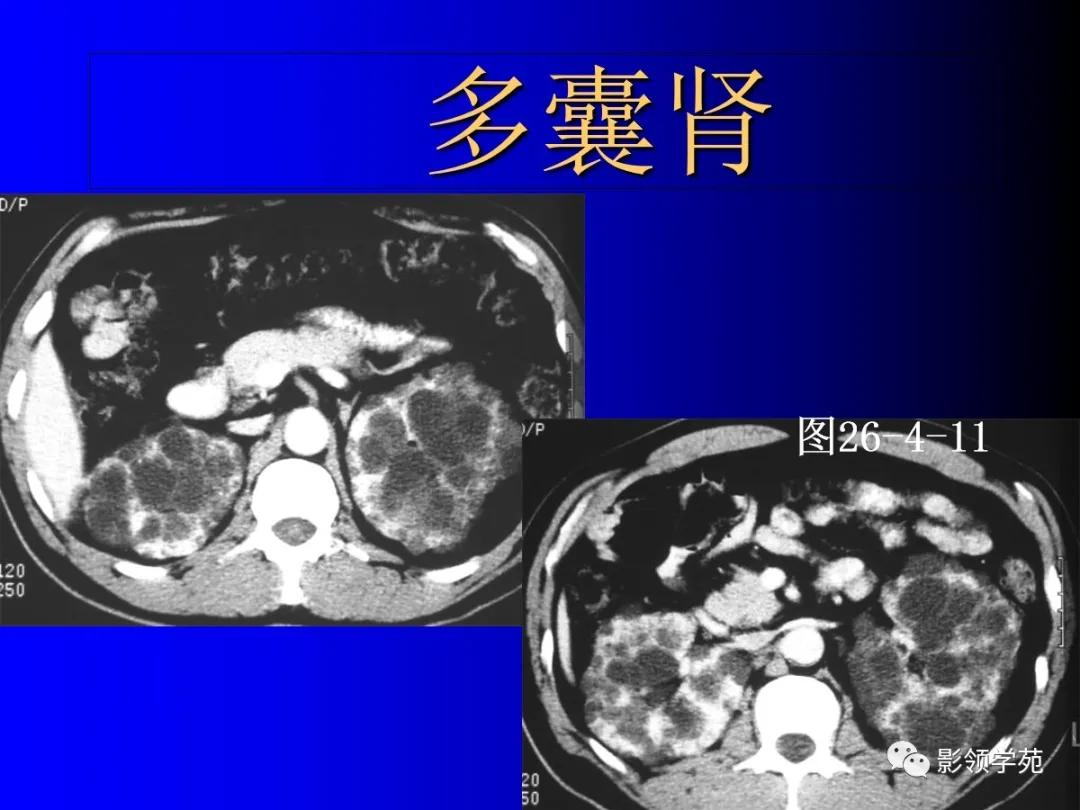

6、常染色体显(隐)性多囊肾

为遗传性肾发育异常。

-

显性者囊肿随年令逐渐增多增大,正常肾组织逐渐减少,患者常在40-50岁左右出现肾功能衰竭。

(隐性者多见于婴幼儿,偶见于青少年,此型常合并先天性肝纤维化,预后差。)